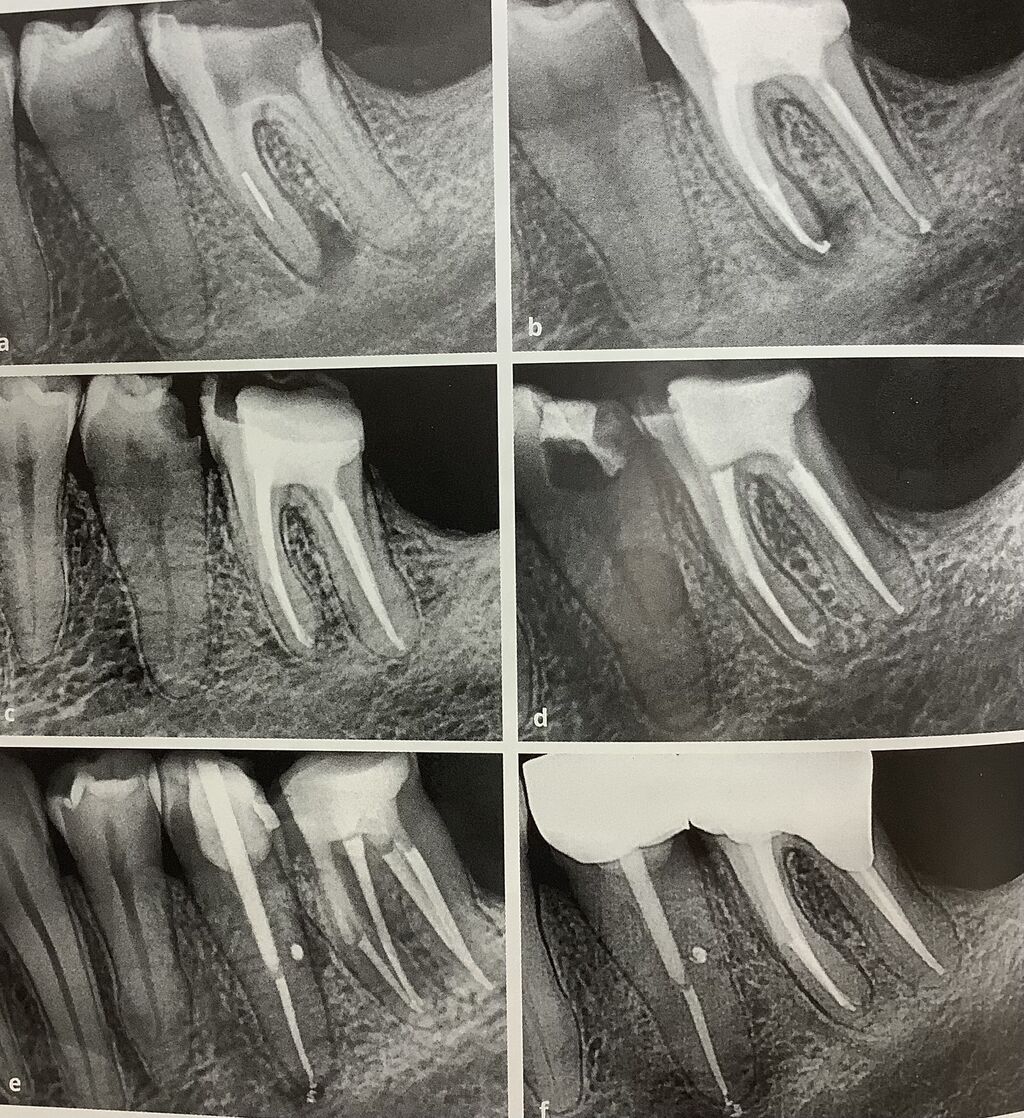

下の左が、根管治療後に直ぐにビルドアップ、コアとポストを立てて

やっと被せてくれました。のが、右下です。